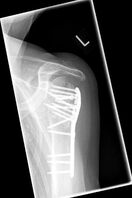

Bei der ersten Vorstellung klagte die 79 jährige Patientin über eine deutliche schmerzhafte linke Schulter und konnte diese kaum bewegen. Die Röntgenbilder zeigten einen fehlverheilten Bruch des Oberarmkopfes mit verschobenen Schrauben nach auswärtiger Nagelosteosynthese. Die operative Behandlung erfolgte mit einem inversen künstlichen Schultergelenk mit einem verlängerten zementfreien Schaft. Die erhebliche Vernarbung stellt eine besondere Herausforderung sowohl innerhalb der Operation als auch in der nachfolgenden Physiotherapie dar.